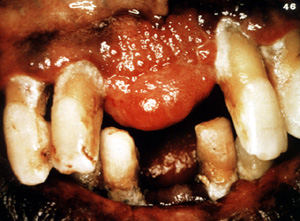

Esta gran lesión se extendió bien en lingual y cambió de sitio algunos de los dientes. Los granulomas periféricos lograrán un tamaño considerable sin tratamiento. La terapia es la biopsia por escisión . Puede ser necesario extender la cirugía  al hueso subyacente para eliminar la lesión. También se indica la eliminación de estímulos irritantes.